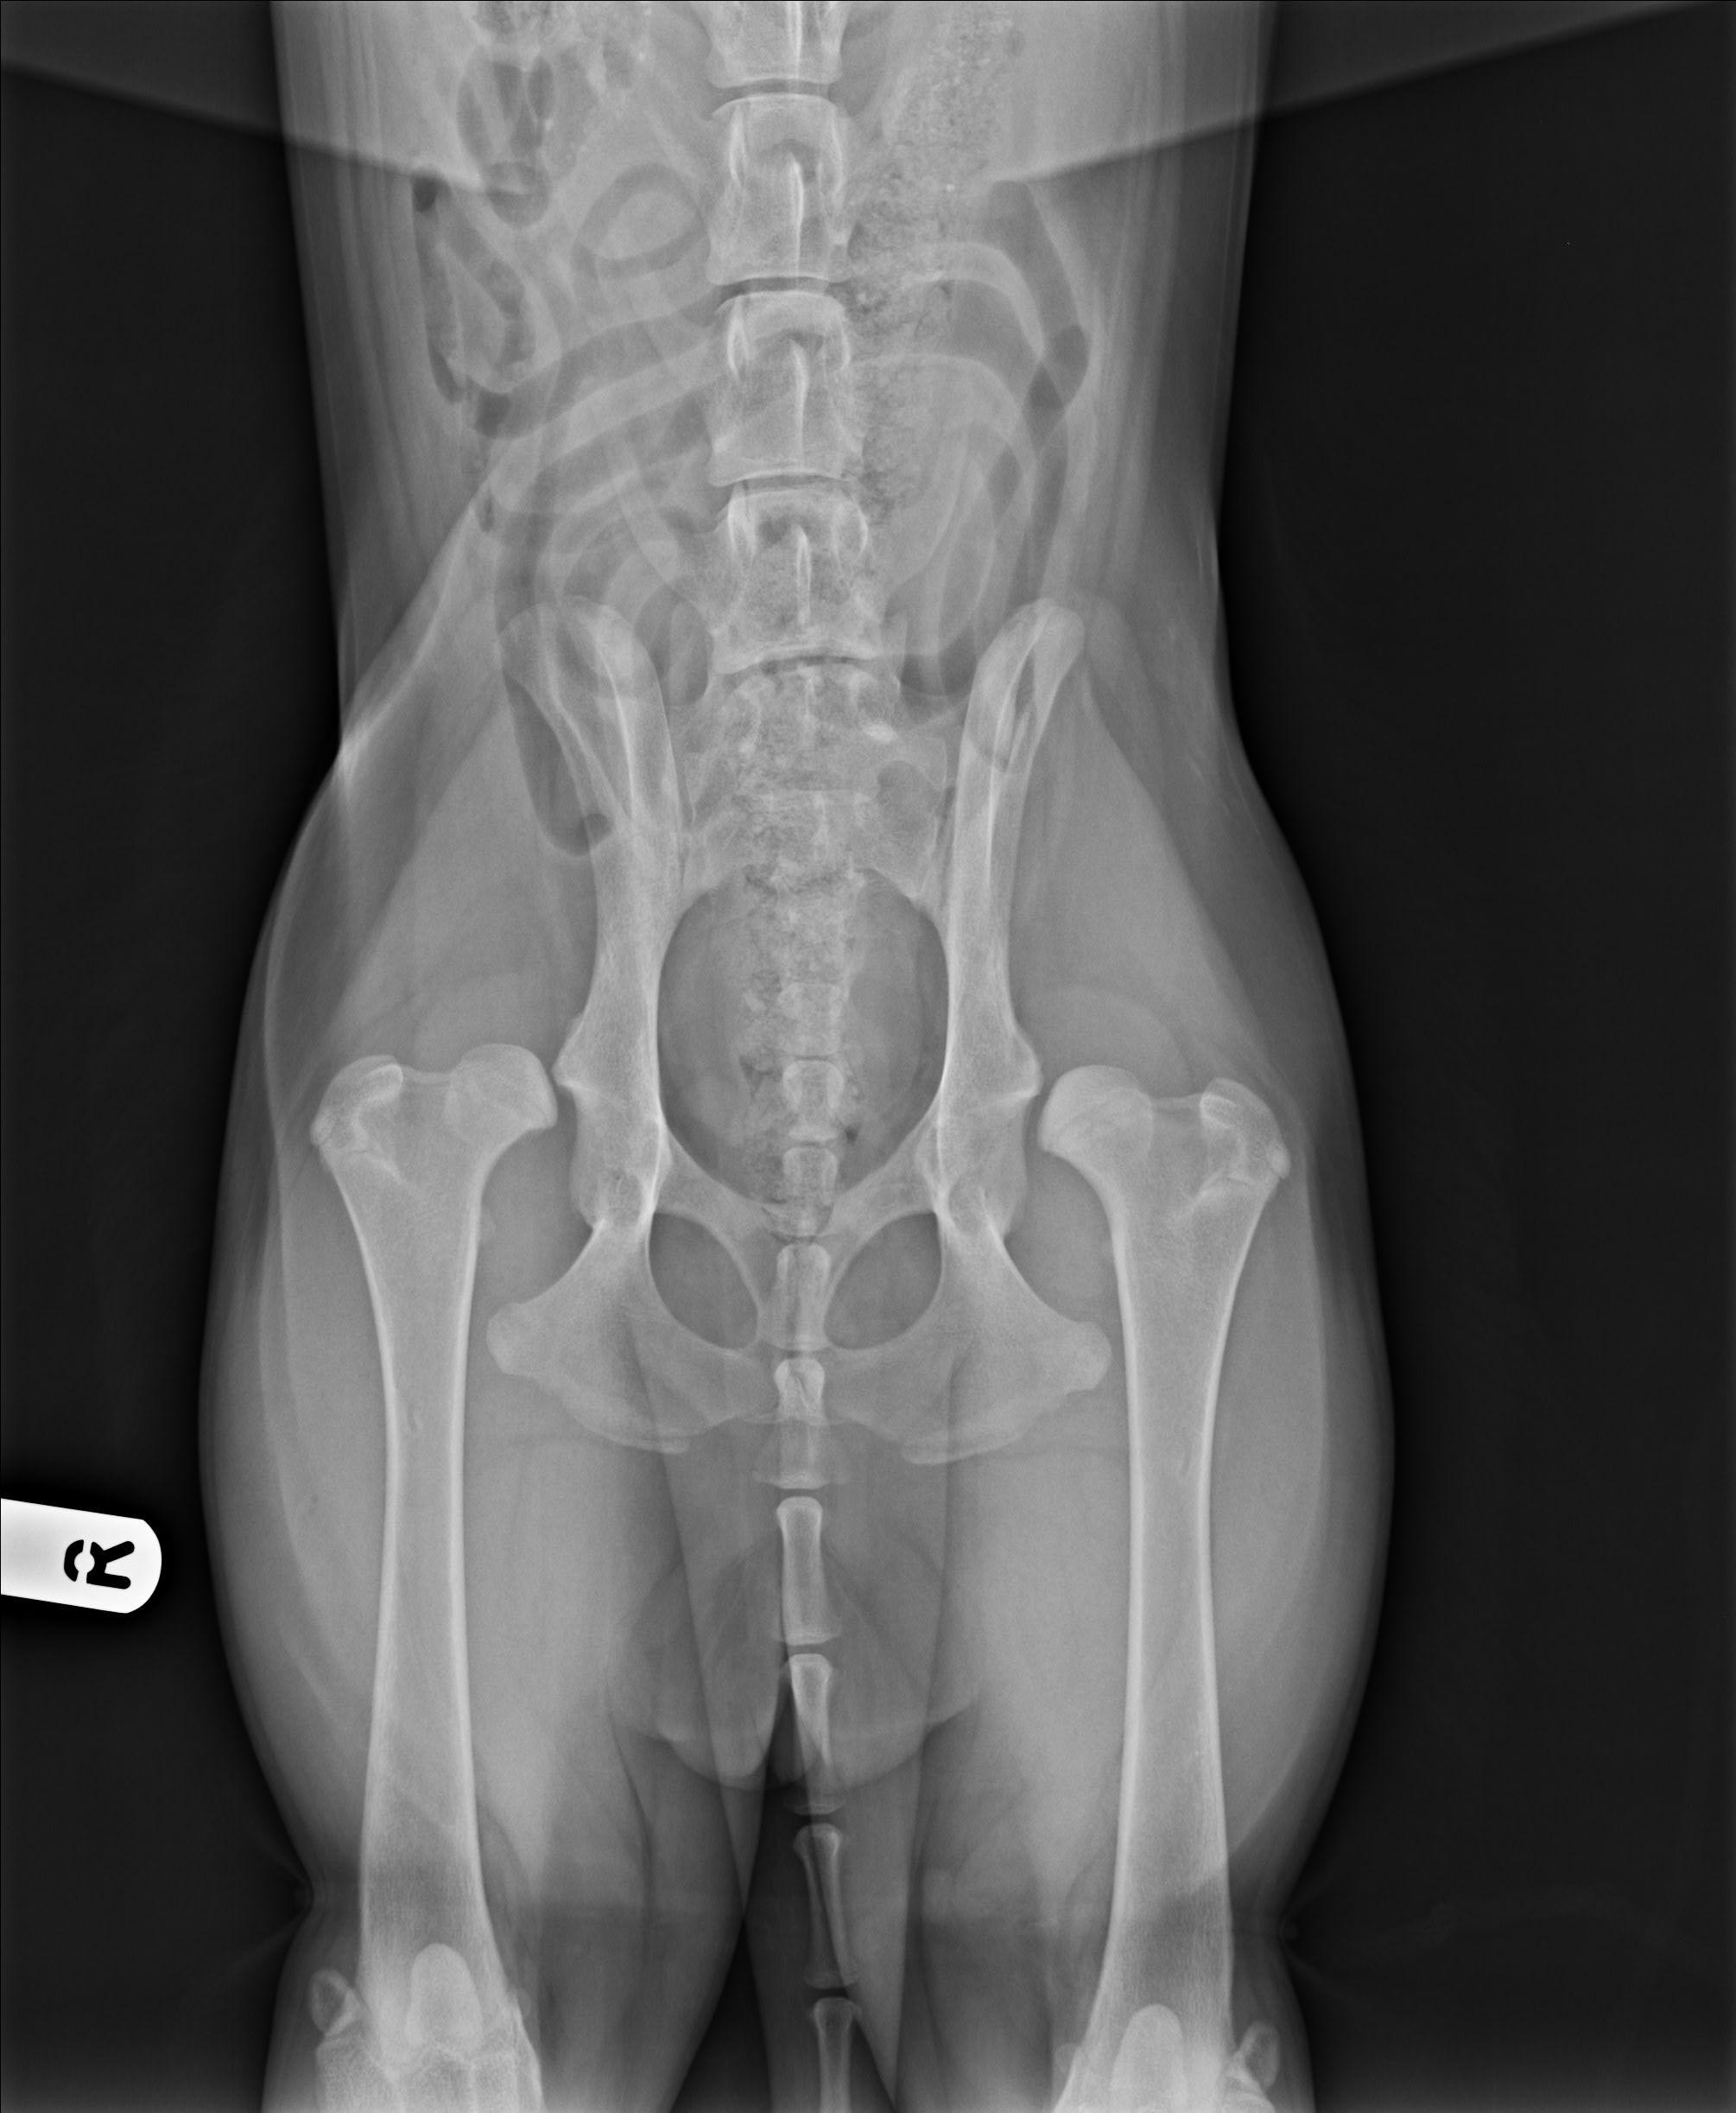

Dobrý den, hafině je sedm měsíců, je to Slovenský čuvač.... a byla ji diagnostikována oboustranná aplazie kyčelních kloubů. V podstatě nám bylo navrhnuto jediné řešení- resekce kyčelních kloubů- tedy asi kyčelních kostí. Chtěla bych se dovědět i názor jiného pana doktora, je toto schůdná možnost? Nechci ji zbytečně trápit, ale kdyby to šlo, bylo by to pro nás určitě lepší řešení, než eutanázie. Bylo mi řečeno, že je resekce docela běžné řešení, ale u menších plemen. Děkuji, za odpověď, Vorobeľová Lucie

Dobrý den, Neviděli jsme rentgen, ale pokud jsou nevyvinuté kyčelní klouby není moc variant, jak psovi a obzvlášť tak velkému plemenu zajistit důstojný život bez neustálých operací, reoperací, hojení, bolesti. Samozřejmě ještě zkonzultujte případ, rtg snímky a psa s ortopedem, ale zvažte, jaký život takového psa čeká. Hodně štěstí

Dobrý den, Štěně bude veselé a hravé do poslední chvile...ale rentgen nelže, tohle není k životu (ani při všech operacích světa) ani při malé a lehké plemeno natož pro 35kilové zvíře....to je opravdu “velká chyba” v chovu. Rozhodnutí je samozřejmě vždy na vás, stejně jako péče o takové štěně. Hodně štěstí